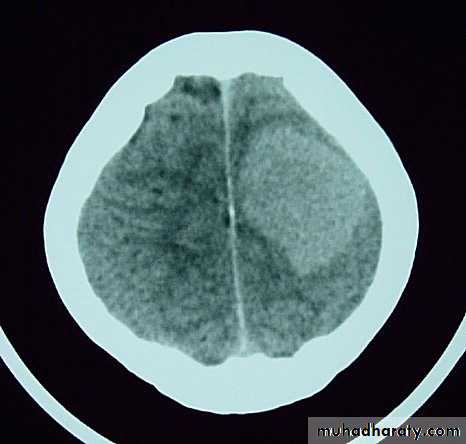

MeningiomaPre contrast CT

MeningiomaPost contrast CT